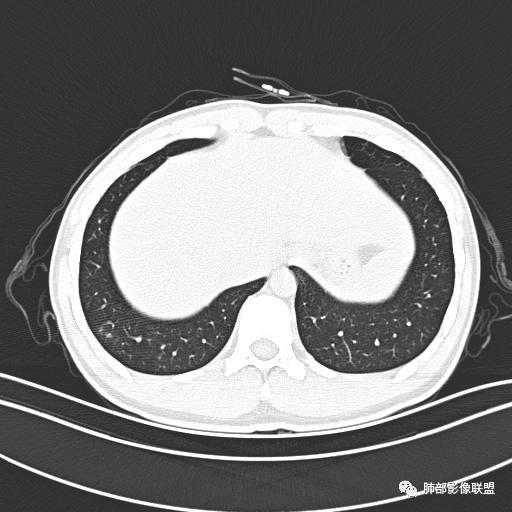

男,19岁

主  诉:发热、全身皮疹2天。

现病史:患者源于2天前受凉后出现发热,最高体温为38.5℃,且颜面部出现少量皮疹,无鼻塞、流涕、咳嗽、咳痰,未在意而未作特殊处理,次日全身皮疹逐渐增多至全身,伴轻度瘙痒,在当地卫生所给予抗病毒、抗感染治疗(具体用药不详)体温有所下降,但皮疹无明显消退,无腹痛、头痛,食欲无明显减退,为进一步诊治,遂于今日急来我院求治,患者目前精神尚可,体力正常,食欲正常,睡眠正常,体重无明显变化,大便正常,排尿正常。

小强:青年,发热,皮疹;双肺散在结节,周围磨玻璃,点晕征,疱疹病毒感染,鉴别荚膜组织胞浆菌,结核。 大雄:青年,急性起病,发热伴全身皮疹2天,抗病毒治疗体温有下降。双肺随机分布大小不等类圆结节,“点晕征”。考虑水痘-疱疹病毒(VZV)血播询问接触史,查体皮疹分布以及形态基本可诊断。 王开金江津中心医院呼吸科:青年男性,起病急,病程短,以发热,皮疹为首发症状,感染指标以单核细胞升高为主,胸部ct双肺多发结界,周围有晕,点晕表现,随机分布,同意於老师意见,水痘疱疹病毒血流感染累及肺。 王秀仙:双肺多发大小不等结节,周围有晕,边缘模糊,呈点晕征表现。青年,急性起病,发热伴全身皮疹2天,抗病毒治疗体温有下降。考虑疱疹病毒。鉴别荚膜组织胞浆菌。 傅昌瑜:19岁男性,发热、全身皮疹2天,单核细胞增高,双肺多发结节,结节边缘见边界不清磨玻璃影。点晕征+发热、全身皮疹+单核细胞增高——考虑水痘-带状疱疹病毒肺炎。 一切∮随缘:年轻男性,发热,皮疹两天,实验室,CRP,PCT增高,影像:双肺多发散在磨玻璃结节,边界欠清,大小不等,呈点晕征改变,以血管束周围分布为主,局部血管束略增粗,其它无明显改变,考虑:1:病毒性肺炎(水痘疱疹病毒?不知道皮肤有无改变)2:真菌(组织胞浆菌,血管侵袭性肺曲霉)3:GPA4:寄生虫(实验室没有看到嗜酸细胞增高) 赵山河:双肺散在结节,周围有晕,边缘模糊,呈点晕征表现。青年,急性起病,发热伴全身皮疹2天,抗病毒治疗体温有下降。考虑水痘—疱疹病毒感染。洪桥爱:青年男性,发热、皮疹2天,伴瘙痒,皮疹于面部首发,之后进展至全身,虽然没有对皮疹进行描述,但是从出疹时间及皮疹进展情况,伴瘙痒,应该就是个水痘患者;CT提示双肺随机分布结节影,部分结节伴有边界不清晕征,考虑水痘血播肺。 刘强:年轻男性,急性起病,皮疹,发热,抗感染治疗体温下降,说明有效。影像表现为散在点晕征,感染类疾病谱(疱疹病毒,真菌,结核),结合年龄,皮肤皮疹,考虑水痘-疱疹病毒性肺炎。 小兜:男性,19岁,发热皮疹两天,颜面部至全身,CRP,降钙素及单核增高。CT示双肺散在小结节,周围伴磨玻璃影,点晕征,考虑为水痘-带状疱疹病毒(varicella-zoster virus,VZV)肺炎 必有路:青年,皮疹+发热+“点晕征”→水痘-疱疹病毒(VZV) 许慧良:青年男性患者,发热、皮疹2天,体温最高38.5℃,第3天皮疹扩展至全身,伴瘙痒,胸部CT:双肺多发随机分布的小结节,结节周边见边界模糊的晕征,考虑水痘病毒感染流心明智:男,19,急性起病,发热伴全身皮疹2天。出疹顺序头→全身,抗病毒有效。胸部CT:两肺多发大小不等类圆形实性小结节影,随机分布,结节周围环绕GGO,边界模糊,呈点晕征。出疹特点是关键,未提示。考虑:血播病毒性肺炎,水痘-疱疹病毒?麻疹?鉴别荚膜组织胞浆菌、TB、血管炎、寄生虫等。 浪迹天涯:病灶多为5-10mm大小结节,结节周围可见磨玻璃样的晕环,常多发,可分布于肺内任何区域,考虑水痘—带状疱疹病肺炎如果短时间内有新的一个区域浸润,更加能说明,